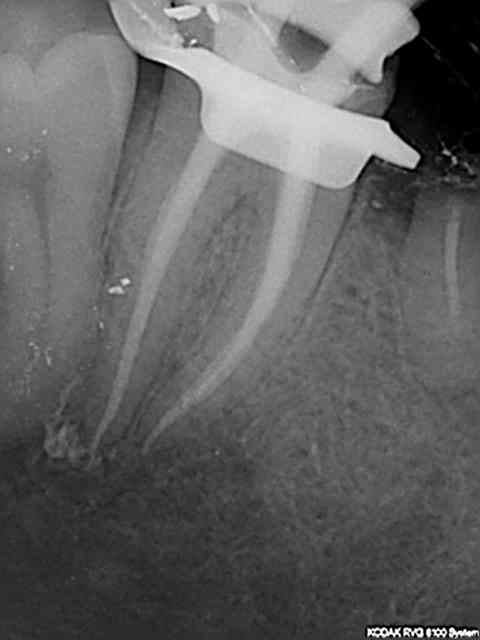

un petit retour sur un traitement canalaire datant de ce matin, voila ma séquence:

-pose de la digue

- dépose du pansement et élargissement Endo -Z

- passage lime 8 10 et 15 et racleur 10 et 15

- radio lime en place

- passage sériel des rotatifs Heroshaper avec lime de cathé entre chaque et rinçage hypochlorite

- Radio cône en place

- Obturation ( finger et Macspadden).

Voila le problème, l'endo ne me satisfait pas, sur les radios lime en place, aucun souci et dès que les cônes entrent dans le jeu tout déraille..

Ou est mon erreur? est ce que j'oublie une étape?

En voila deux supplémentaires, impossible de retrouver la dernière j'ai du l'enregistrer sur un autre dossier, je cherche ça.

On voit bien le cône dans le palatin qui bloque..

A vrai dire c'est surtout le palatin qui me gêne au niveau longueur, je trouve les deux autres pas trop mal (mis a part la condensation que je trouve encore très moyenne..)